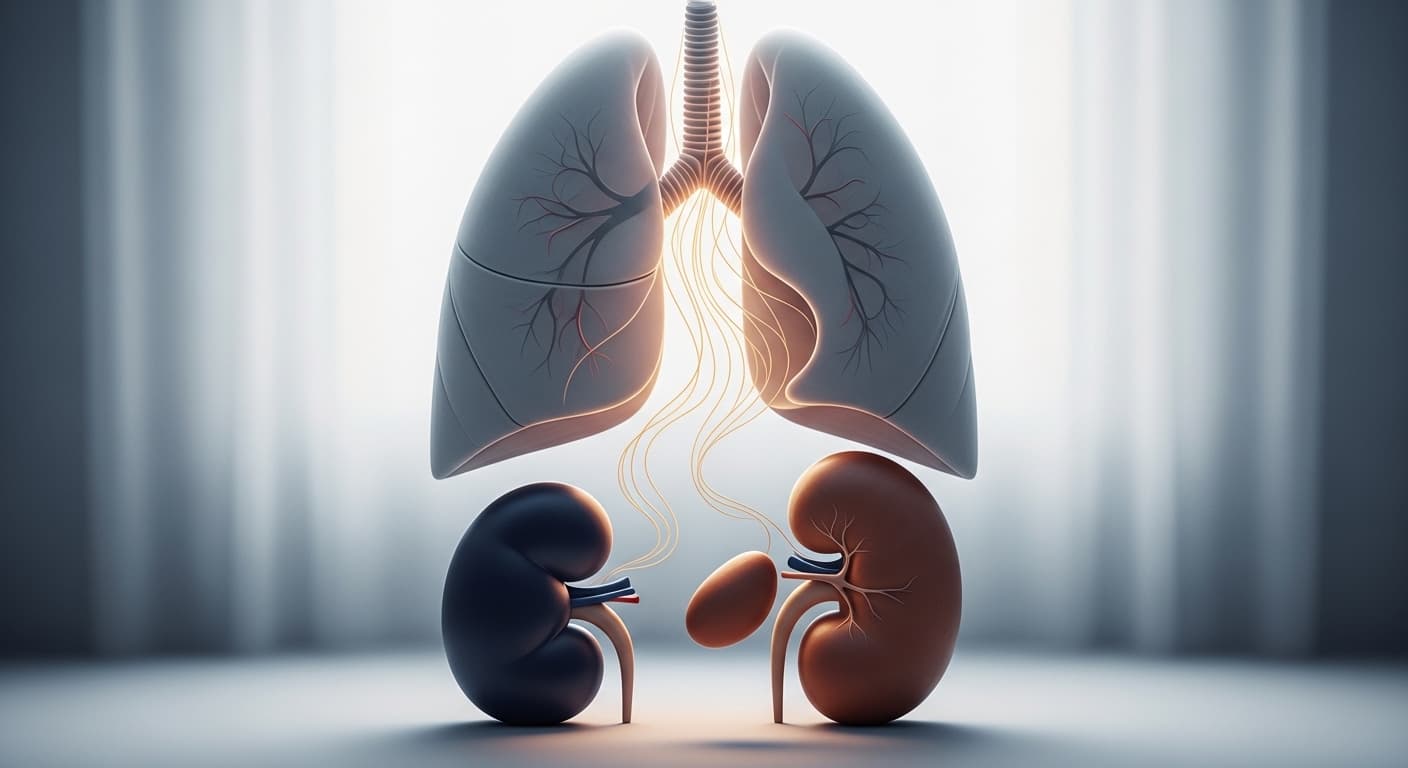

"밤새 콜록콜록 기침하느라 잠 한숨 제대로 못 자고, 아침엔 가슴이 턱 막혀 숨쉬기조차 버거웠던 경험, 혹시 있으신가요? 숨이 차고 쌕쌕거리는 소리에 잠결에도 가슴이 조여오는 듯한 기분… 혹시 ‘나도 천식인가?’ 걱정하셨다면, 오늘 제 이야기에 귀 기울여 주세요."

喘者, 肺實也, 肺氣壅塞, 呼吸迫促, 鼻竅煽動, 有聲曰喘.

천이란 폐가 실하여 폐 기운이 막히고 숨쉬기가 촉박하며 콧구멍이 움직이고 소리가 나는 것을 이른다.